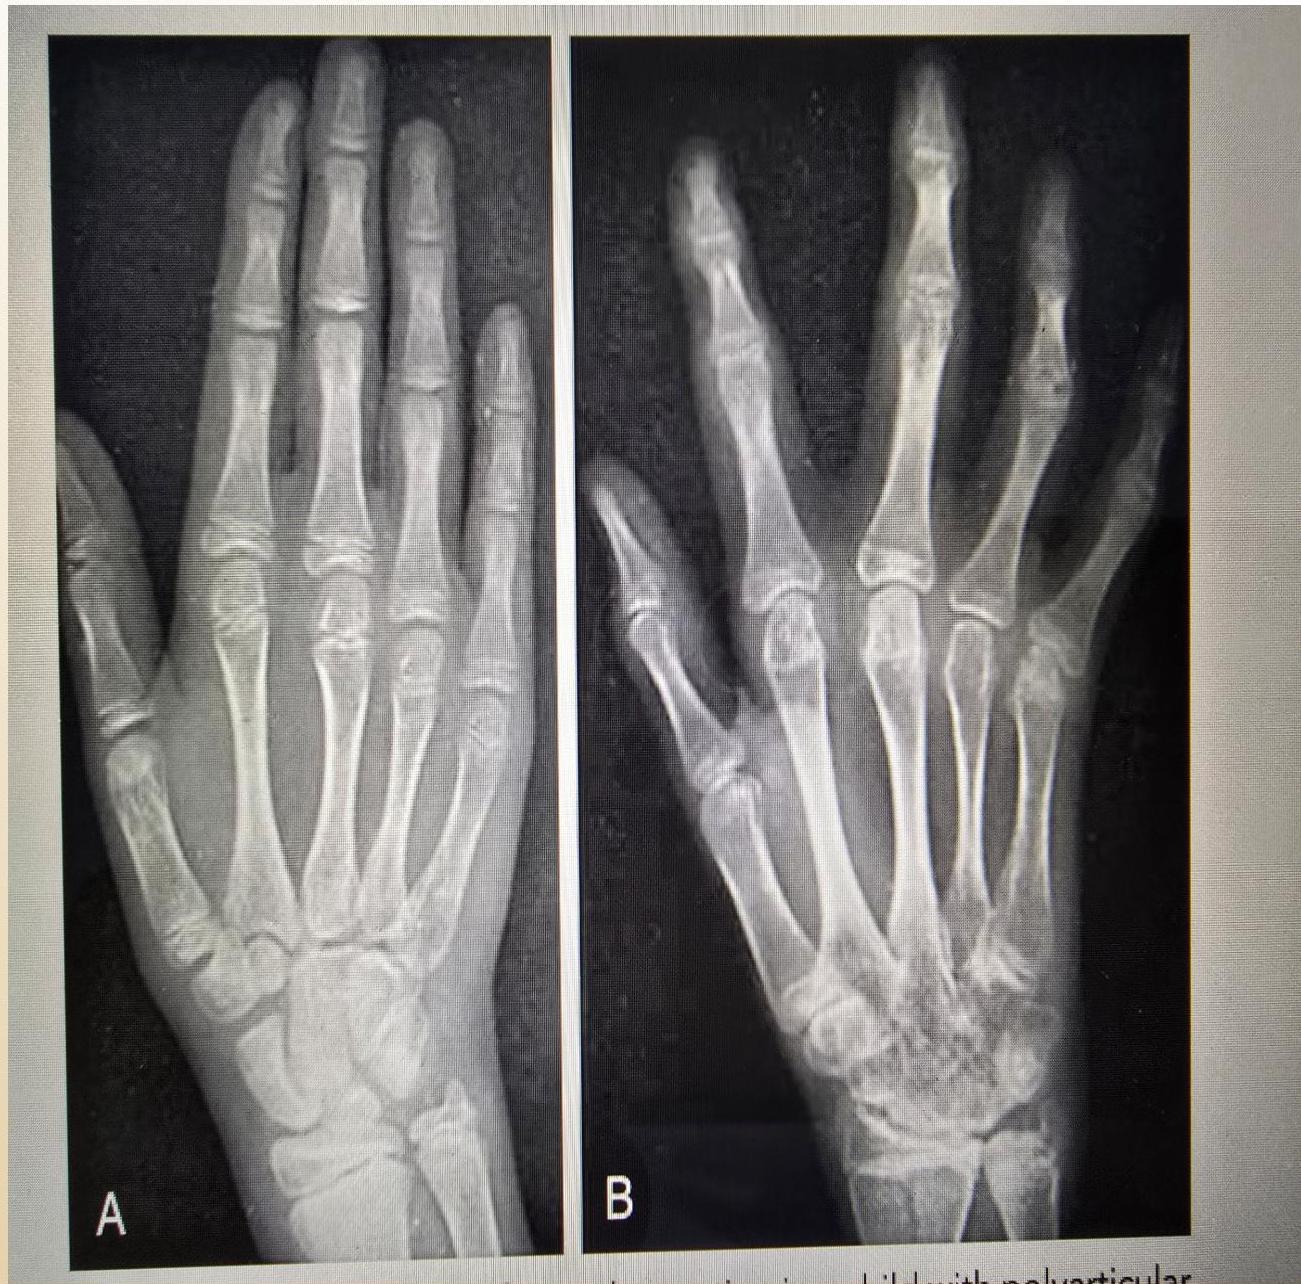

Radiographic Progression (Examples)

Hand Progression: A: Radiograph at onset. B: 4 years later - Loss of articular cartilage, destructive changes in distal/proximal interphalangeal and metacarpophalangeal joints, destruction and fusion of wrist bones.

(Left: Patient with active polyarticular arthritis. Right: Radiographic progression)